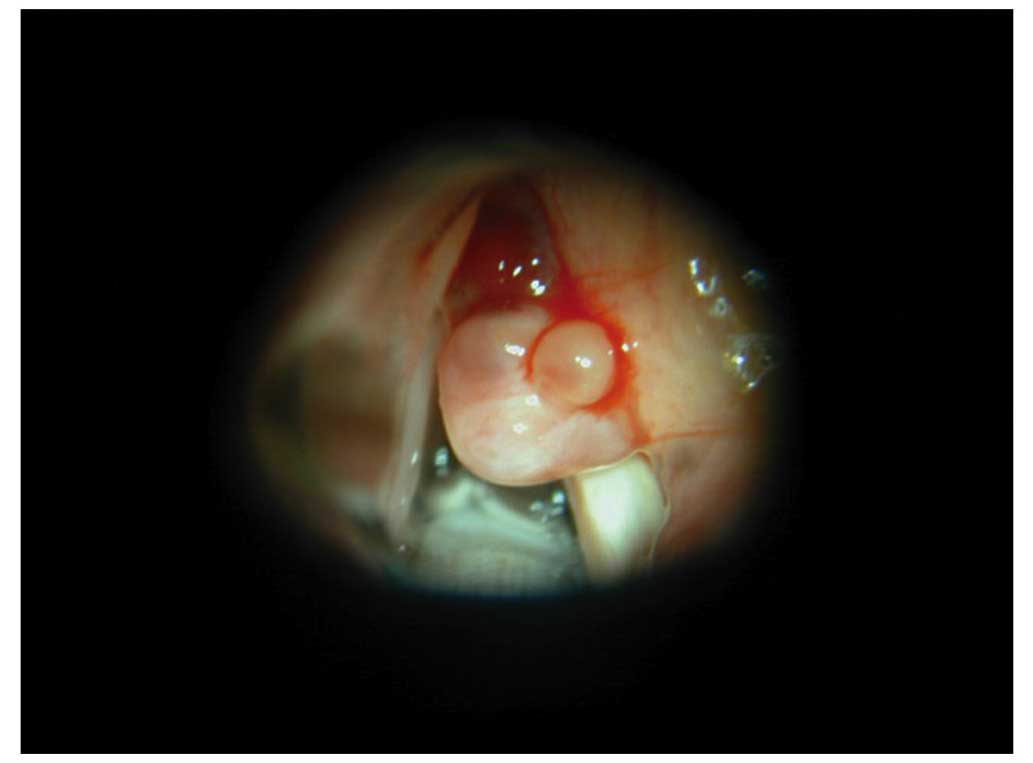

Consequently, microscopic surgery was performed under general anesthesia after admission to Nagoya Daini Red Cross Hospital on June 28, 2001. The base of the tumor mass was identified in the right laryngeal ventricle (Fig. 1), and dissected from the mucosa. The tumor was resected, and subsequently a potassium titanyl phosphate laser beam was applied to the tumor resection and the mucosa around the tumor. A diagnosis of pPNET was reached following pathological examination. Paraffin sections revealed sheets of small round cells, which possessed relatively regular nuclei and sparse cytoplasm. The nuclei demonstrated a salt and pepper chromatin pattern, and the nucleoli were obscured. Abortive Homer-Wright rosettes were rare, and no other specific patterns were identified. A relatively high frequency of mitotic figures was observed, while a Periodic Acid Schiff stain indicated that no glycogen was present (Fig. 2A). Immunohistochemical studies revealed that tumor cells were positive for cluster of differentiation 99 (CD99), neuron-specific enolase (NSE), S100 protein and vimentin, and negative for cytokeratin (AE1/AE3, CAM5.2), epithelial membrane antigen, muscle-specific actin, α-smooth muscle actin, desmin, leucocyte common antigen, chromogranin A and synaptophysin (Fig. 2B; Table I). An ultrastructual study revealed that the tumor cytoplasm contained a reduced number of mitochondria. Other organelles were not well developed; no electron dense core granules were detected, and nuclei were round with obscured nucleoli.

Figure 1.

Intraoperative image of the area above the right vocal cord. The mass was based at the right laryngeal ventricle. The tumor was soft and easily hemorrhagic.